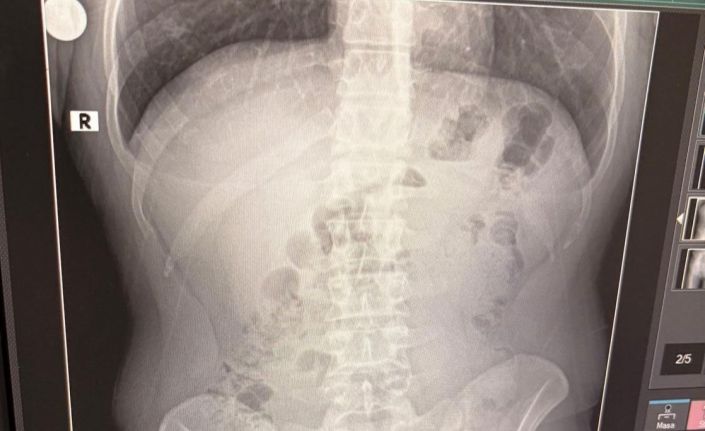

Adreste yapılan arama sırasında ekipler, şüphelilerden birinin üstünde 1 adet kapsül ele geçirdi. Şüphe üzerine tüm şüpheliler hastaneye götürüldü ve yapılan röntgen kontrollerinde 3 kişinin midelerinde kapsül içine gizlenmiş metamfetamin tespit edildi.

Hastanede tedavi altına alınan şüphelilerin vücudundan kapsüller çıkarılırken, adreste ele geçirilenlerle birlikte toplam 1 kilo 516 gram metamfetamin ele geçirildi.